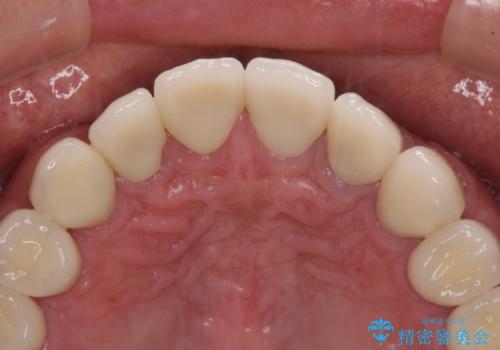

当初は前歯6歯をオールセラミッククラウンで補綴する予定でしたが、前歯が綺麗に仕上がったことで、奥歯まで延長して補綴することとしました。

黄ばんだ前歯や白すぎたクラウン、プラスチックの継ぎ接ぎなどを全てオールセラミッククラウンの統一感のある前歯に仕上げました。